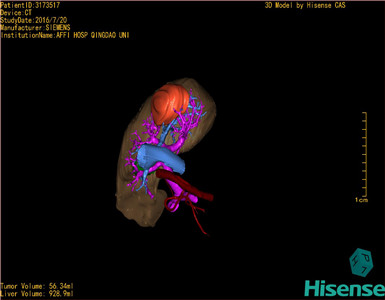

通过调节窗宽窗位调整CT序号,对肿瘤,肝实质,胆囊,下腔静脉,肿瘤,肝动脉、门静脉及肝静脉等进行三维重建;系统自动计算肿瘤体积和肝脏体积。

模拟手术操作,自动计算切除肿瘤体积。肝脏体积为928.9ml,肿瘤体积为56.34ml,肿瘤体积为肝脏体积的6%,通过比对60-70岁正常肝脏体积为1262.7±284.31 ml,通过术前模拟手术,精准判断切除后剩余肝脏体积能耐受,避免肝衰竭发生。

术前三维重建:

重建图片